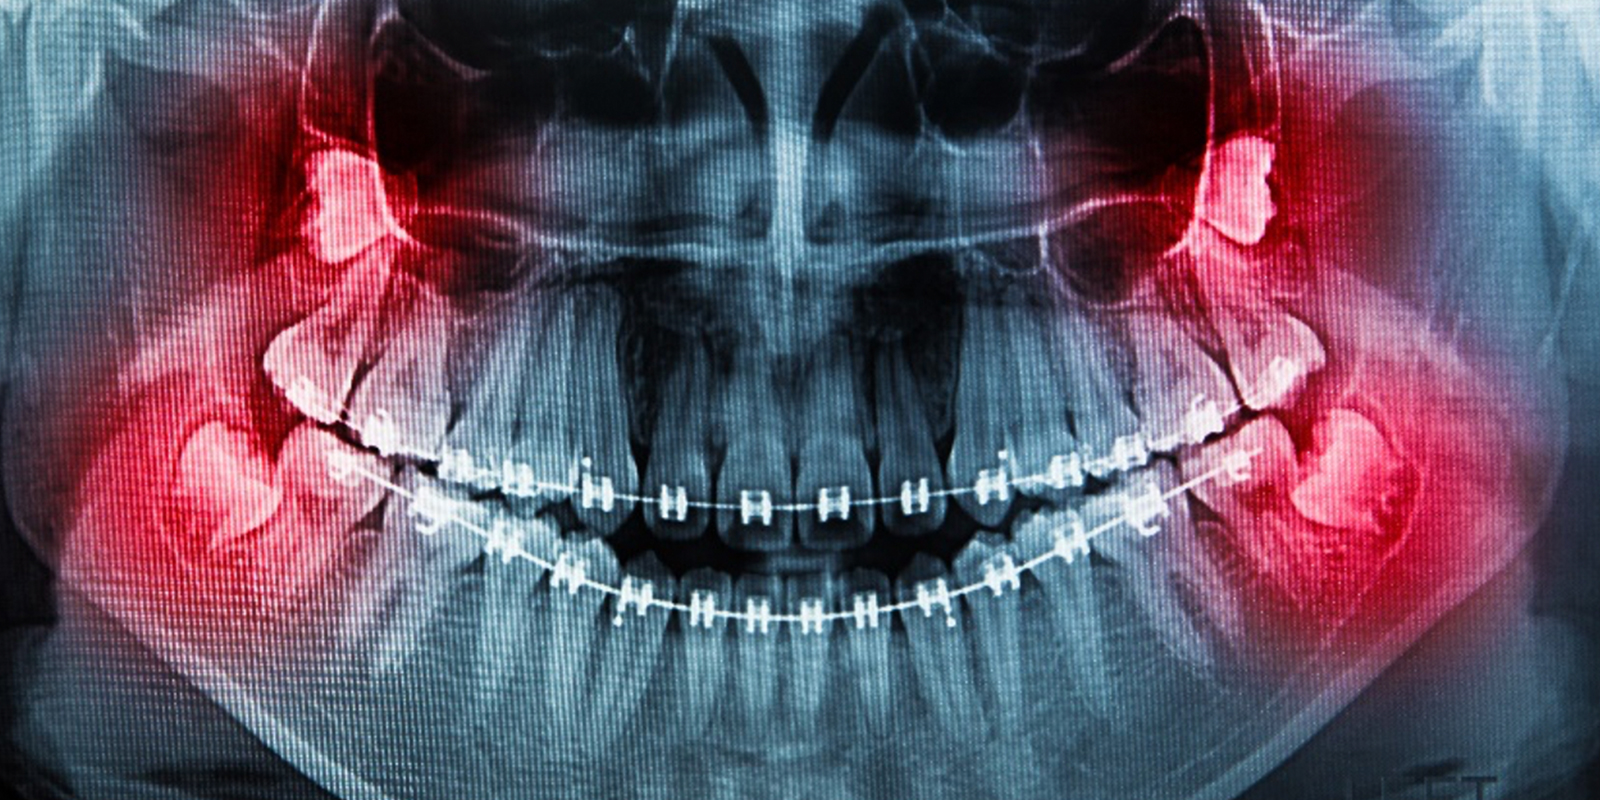

親知らずが上下左右ある方のレントゲン画像

親知らずの抜歯は、麻酔をしてから行います。針を歯ぐきに刺すので、一瞬チクっとした痛みがありますが徐々に麻酔が聞いてきて親知らずの周りの感覚がなくなります。歯ぐきを切って抜歯をする場合は抜歯後、麻酔が切れるとズキズキとした痛みが出る場合がありますが、痛み止めなどを処方してもらえます。

また、歯ぐきを切る場合、主に下の親知らずを抜歯すると顔が腫れることがあります。抜歯後、2日間ぐらいが腫れのピークです。もしも大事な予定などがあれば、歯科医と相談して抜歯の日を決めることをおすすめします。